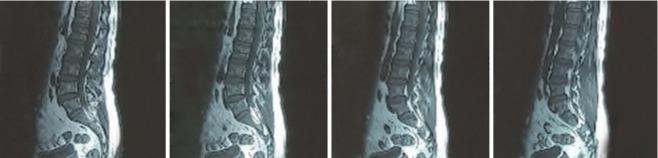

A 43-year-old male, office worker with history of chronic radicular low back pain radiating into the left leg was admitted to a sports medicine research center, neuroscience institute. During the past year, he visited a physiotherapist and orthopedic experts. Magnetic resonance imaging revealed a protruded disc at L4-5 level. Additionally, electromyography indicated that there was bilateral moderate irritation at the L5-S1 root. We designed a management package including exercise therapy, dry needling, and nonfunctional electrical stimulation for four sessions. Outcomes included pain intensity, pain with lumbar flexion, with the numerical rating scale (NRS), visual analogue scale (VAS), and function measured with the Oswestry Disability Index before and after the intervention. After 4 treatment sessions, the patient reported a reduction in pain intensity from a 9 to 2 on the NRS and from 90 to 30 on the VAS. In addition, the patient was able to perform lumbar flexion fully without pain.

一名43岁男性,办公室职员,有慢性神经根型腰痛并向左下肢放射的病史,被收治于一家运动医学研究中心,即神经科学研究所。在过去一年里,他拜访了物理治疗师和骨科专家。磁共振成像显示L4 - 5节段椎间盘突出。此外,肌电图显示L5 - S1神经根存在双侧中度刺激。我们设计了一个包括运动疗法、干针疗法和非功能性电刺激的治疗方案,共进行四个疗程。结果指标包括疼痛强度、腰椎前屈时的疼痛情况,采用数字评分量表(NRS)、视觉模拟量表(VAS)进行评估,以及采用Oswestry功能障碍指数在干预前后对功能进行测量。经过4个疗程的治疗后,患者报告疼痛强度从NRS的9分降至2分,VAS从90分降至30分。此外,患者能够完全无痛地进行腰椎前屈。